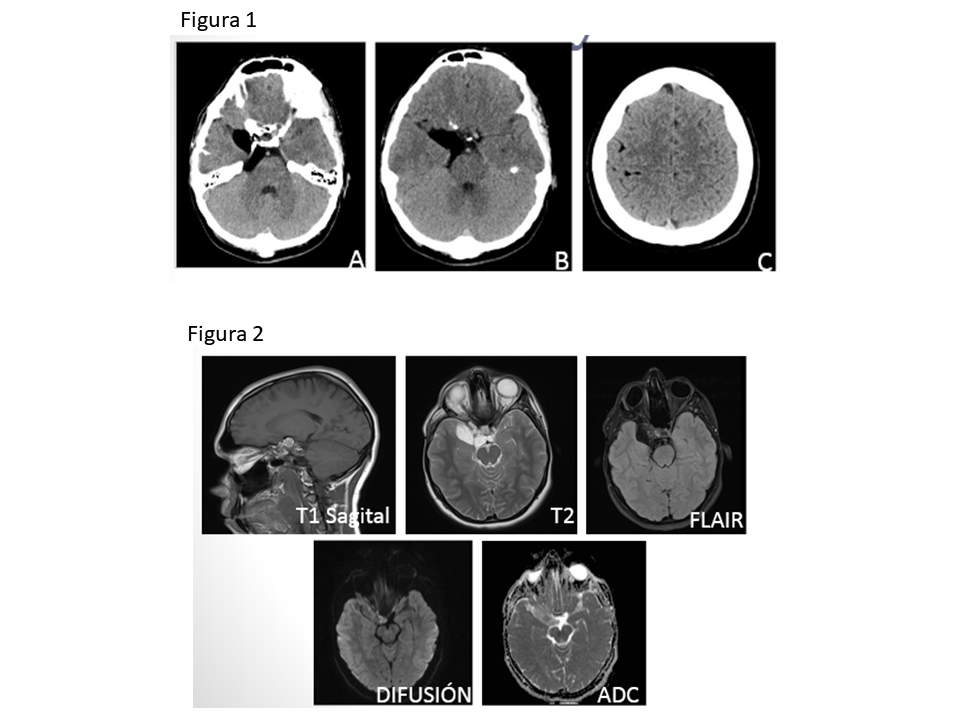

Figura 1: TC secuencial de cráneo sin contraste intravenoso. Cortes en plano axial.

A y B: Lesión quística de densidad grasa en cisterna prepontina derecha que se extiende hacia la fosa craneal media y seno cavernoso.

C: Lesiones de densidad grasa de pequeño tamaño en el espacio subaracnoideo, adyacentes a surcos hemisféricos bilaterales, más llamativos a nivel frontal derecho.

Figura 2: RM cerebral.

Masa que ocupa la cisterna perimesencefálica, de bordes bien definidos que se extiende hacia fosa craneal media. Es hiperintensa en T1 y T2, suprimiendo su señal en FLAIR y no restringe en difusión.